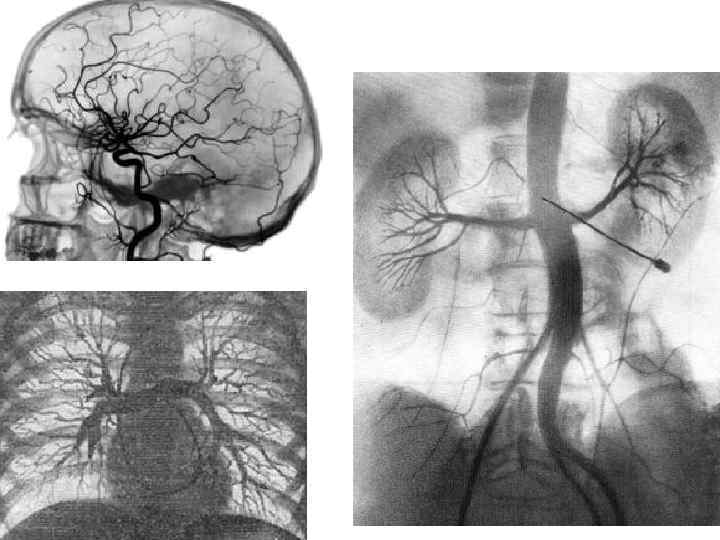

Ангиография • Ангиография - это метод контрастного рентгенологического исследования кровеносных сосудов. • Ангиография изучает Ангиография • Ангиография - это метод контрастного рентгенологического исследования кровеносных сосудов. • Ангиография изучает функциональное состояние сосудов, окольного кровотока и протяженность патологического процесса.

Как выполняется ангиография Методика ангиографического исследования заключается во введении в сосудистое русло рентгеноконтрастного вещества. Как выполняется ангиография Методика ангиографического исследования заключается во введении в сосудистое русло рентгеноконтрастного вещества. Сразу же при введении этого вещества производится серия рентгенологических снимков. В зависимости от вида ангиографии место ввода контрастного вещества может быть разным. Для визуализации патологии артерий – артериографии, контраст вводится через прокол в паховой складке или в подмышечной области (в зависимости от уровня сосудов). Для визуализации патологии вен – флебографии – прокол, в основном, делается в области стопы. Флебография чаще всего применяется для диагностики осложнений варикозной болезни и выявления тромбозов. Накануне перед ангиографией пациент прекращает прием пищи.